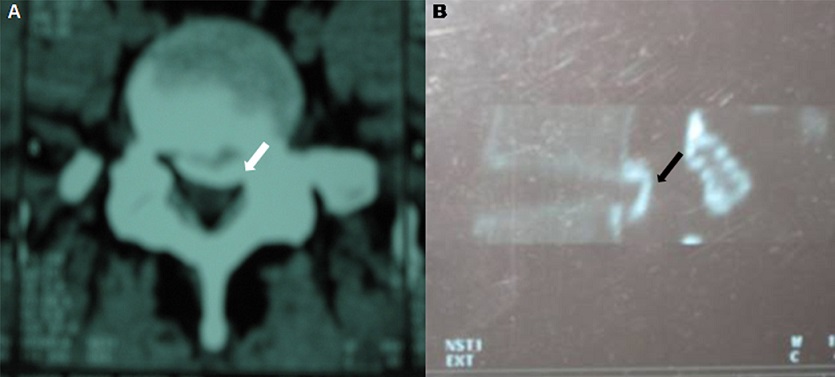

L'ossification du ligament vertébral commun postérieur (LVCP) est une pathologie hyperostosante relativement fréquente chez les sujets japonais, ce qui lui a valu la dénomination de « maladie japonaise ». Elle est caractérisée par une ossification hétérotopique au sein du LVCP pouvant aboutir à une compression médullaire et à une myélopathie sévère. Elle est le plus souvent de localisation cervicale et doit amener à chercher prioritairement une anomalie du métabolisme phosphocalcique, en particulier un rachitisme vitamino- résistant hypophosphatémique familial ou une hypoparathyroïdie, une hyperostose vertébrale engainante ou une chondrocalcinose articulaire. Nous rapportons un cas exceptionnel d'ossification du LVCP de localisation lombaire chez un patient tunisien. Il s'agissait d'un homme de 30 ans, sans antécédents pathologiques, adressé à l'unité de Médecine physique pour une lombosciatique S1 gauche tronquée évoluant depuis 3 mois et gênant la station assise et les activités de la vie quotidienne. Il n'y avait pas de trouble vésico-sphinctérien, ni de limitation de périmètre de marche. L'examen montrait un syndrome rachidien avec un signe de Lasègue positif à gauche. L'examen neurologique et des articulations périphériques était normal. Les radiographies standard du rachis lombaire montraient une ossification du LVCP lombaire à l'étage L5 et S1. Le scanner du rachis lombaire confirmait la calcification du LVCP en L5 et S1 avec un effet de masse sur le contenu canalaire essentiellement en postéro-para-médian gauche. Le bilan étiologique, phosphocalcique, était négatif. Une laminectomie de décompression du rachis lombaire et une excision de l'ossification étaient réalisée suivi d'une rééducation adaptée. L'évolution était favorable avec disparition complète de la symptomatologie.